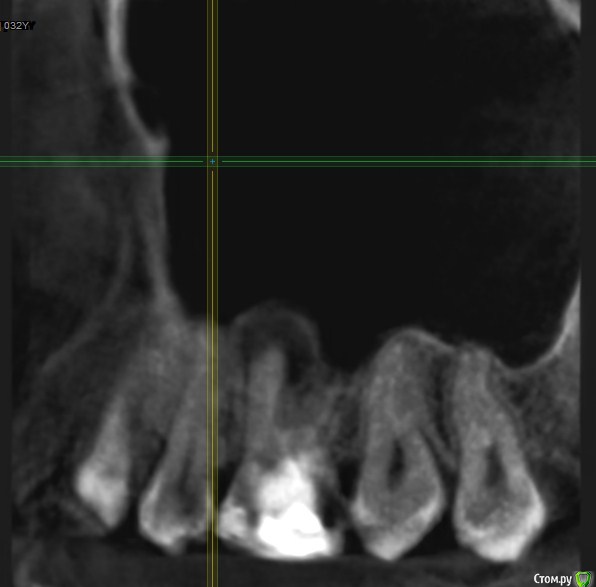

Подскажите, пожалуйста, точно удалять? Как принять это решение, все таки надежда на какой то другой лечебный вариант теплится =)post-59509-0-08196600-1578493080_thumb.jpgpost-59509-0-63211400-1578493088_thumb.jpgpost-59509-0-77705800-1578493096_thumb.jpgpost-59509-0-02698500-1578493106_thumb.jpgpost-59509-0-04880900-1578493120_thumb.jpgpost-59509-0-11411000-1578493128_thumb.jpg

По представленным срезам создаётся впечатление, что лечение вполне возможно